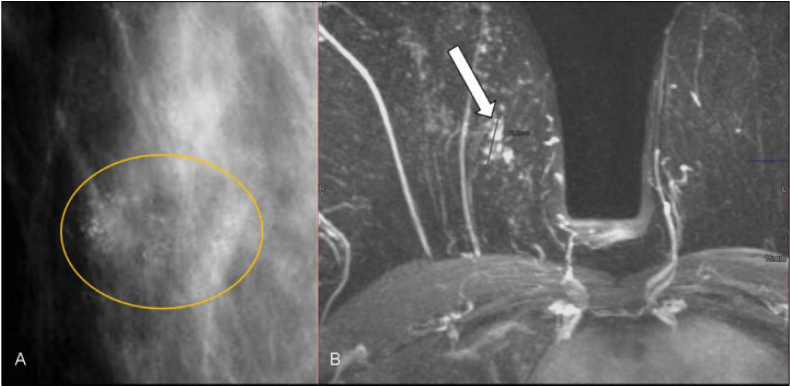

Hiperplasia ductal atípica y carcinoma intraductal. Mujer de 72 años, asintomática. Mamografía digital. (A) Cúmulo de microcalcificaciones amorfas y lineales finas (delimitadas por círculo amarillo). (B) RM tras introducir contraste intravenoso. Realce con distribución focal, en empedrado que coincidió con las microcalcificaciones descritas, criterios sospechosos de malignidad (flecha). Se realizó BAV con guía esterotáxica, con resultado de hiperplasia ductal atípica. Al realizar extirpación completa de las microcalcificaciones el resultado definitivo fue de carcinoma intraductal de alto grado.